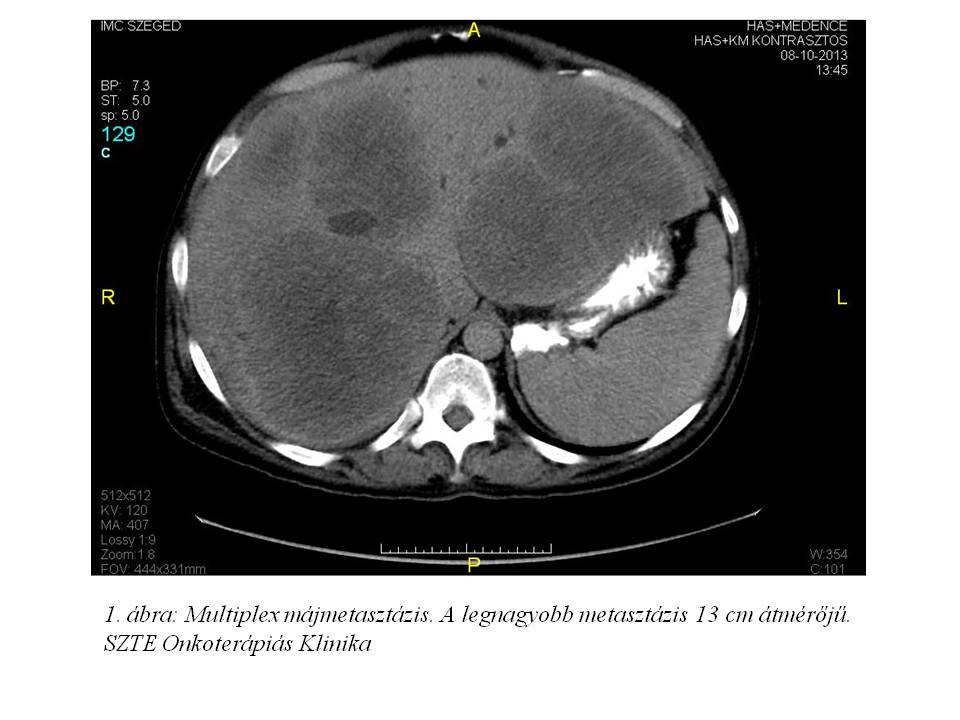

2013 októberében vérszékelés, hasi fájdalom, kb. 10 kg-os fogyás (10%-ot meghaladó súlyvesztés), emelkedő májfunkciós értékek (GOT: 65 U/l, GPT: 67 U/l, GGT: 631 U/l, ALP: 580 U/l, sebi: 34.5 umol/l, dibi: 25.5 umol/l) miatt indult kivizsgálása. Has-kismedence CT (2013.10.08., 1. ábra, 2. ábra, 3. ábra) készült, mely leírta a rectum-sigma átmenet lumenbe domborodó tumorát, multiplex máj metastasist, ascitest. Mellékleletként felvetette a jobb tüdő bázison lévő metasztázis gyanúját. Colonoscopia (2013.10.11.) során a sigmában, az anusgyűrűtől 25 cm-re egy vastag nyélen lévő 6-7 cm-es polyp volt látható. Mivel nem tűnt invazív tumornak, az SZTE Sebészeti Klinikán polypectomiát végeztek. A szövettan azonban malignusan transformálódott tubulovillosus adenomát igazolt adenocarcinomával (pT1). A T1-es kategóriájú daganat multiplex áttétképzését a beteg immunszuprimáltsága magyarázza.